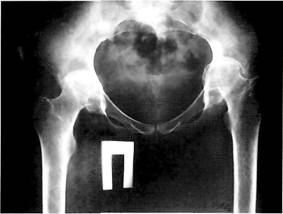

Рис. 7. Рентгенограмма больной с двусторонней дисплазией тазобедренных суставов. Кранеолатеральная инклинация вертлужных впадин, недопокрытие головок бедренных костей. Начальные признаки коксартроза: субхоидральный склероз крыши вертлужной впадины, незначительное сужение суставной щели.

Рентгенологическая картина диспластического коксартроза зависит от выраженности анатомических изменений (различают вывих, подвывих и дисплазию) и стадии заболевания. На ранних стадиях превалируют признаки анатомических нарушений в суставе: вертлужная впадина обычно плоская со скошенной крышей (т.н. краниолатеральная инклинация крыши вертлужной впадины), УВН больше нормы (рис. 7).

Ацетабулярная дисплазия чаще всего сочетается с coxa valga и избыточной антеверсией шейки бедренной кости, что приводит к перегрузке переднего отдела сустава, растяжению капсулы. Нестабильность тазобедренного сустава определяется по уменьшенному углу Виберга (диагностическое значение имеет угол менее 20°), нарушению линии Шентона, недопокрытию головки бедренной кости. Неблагоприятное, с точки зрения биомеханики, распределение нагрузок в суставе вызывает постоянное смещение головки вверх и латерально, избыточное давление на ограниченный участок вертлужной впадины и головки бедренной кости. В результате этого, с одной стороны, происходит развитие кист на месте концентрации напряжения (как правило, это симметричные участки в головке и крыше вертлужной впадины), с другой, развиваются оссификаты на месте постоянного напряжения капсулы сустава - в области прикрепления хрящевой губы к краю вертлужной впадины и нижнего отдела головки бедренной кости и вертлужной впадины.

При дальнейшей нагрузке происходит постепенная деформация головки бедренной кости; она смещается вверх, ротируется кнаружи и приводится, что клинически соответствует развитию стойкой сгибательно-приводящей контрактуры сустава (рис. 8).